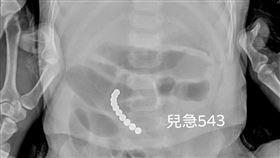

男童嘔吐3天 腸子切開赫見熱門玩具

又有小朋友誤食熱門玩具「巴克球」,中部一名1歲多男童...